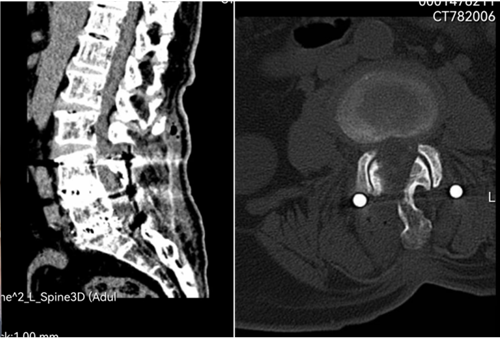

患者胡某术前影像

UBE椎管减压术后小切口

UBE椎管减压术后影像显示椎管双侧减压充分、关节突保护良好